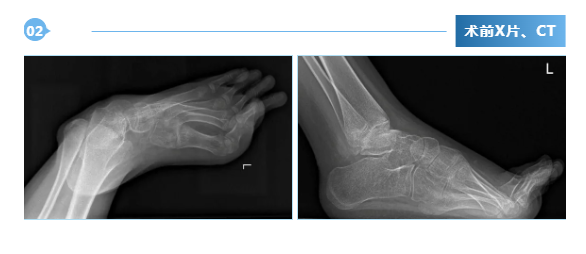

广东医附院创伤骨科成功开展ilizarov技术,治疗脑瘫马蹄足畸形

近日,我院创伤骨科在吴浩俊主任医师的带领下,由陈继铭、刘田丰、陈周韬、潘开翔等组成的足踝医师技术团队,在麻醉手术中心、创伤骨科护理团队的共同努力下,成功为1名脑瘫后马蹄内翻足畸形患者成功实施了 ilizarov环形外固定架矫形手术。患者黎某某,女,12岁,因“双...2024-05